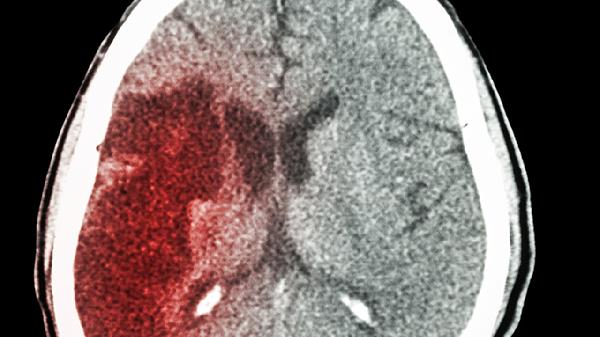

从躺到站的体位变化,会让血压在3秒内升高20-30mmHg。临床数据显示,清晨6-10点脑梗发生率比其他时段高40%。